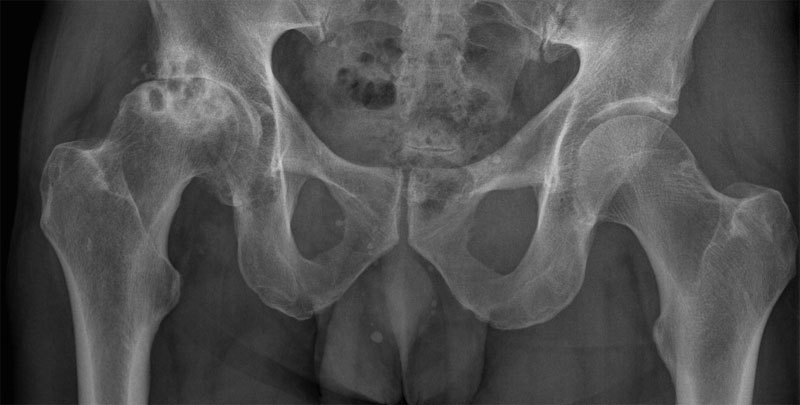

Рентгенологическое исследование

Стадия коксартроза устанавливается проведением рентгенографического исследования. На полученных изображениях отчетливо просматриваются деструктивные изменения в тазобедренном суставе. Это сужение суставной щели, деформация костных поверхностей, формирование остеофитов.

Для каждой стадии характерна своя симптоматика, выраженность которой зависит от степени сужения суставной щели, количества образовавшихся костных наростов.

| Степень тяжести коксартроза | Характерные симптомы и рентгенографические признаки |

| Первая | Суставная щель сужена неравномерно, вокруг вертлужной впадины сформировались единичные остеофиты. Возникают слабые дискомфортные ощущения, но чаще заболевание клинически не проявляется |

| Вторая | Суставная щель сужена почти в 2 раза, головка бедренной кости смещена, деформирована, увеличена, а костные наросты обнаруживаются даже за пределами хрящевой губы. Боли в бедре становятся постоянными, сопровождаются значительным ограничением подвижности |

| Третья | Полное или частичное сращение суставной щели, множественные костные разрастания, расширение головки бедренной кости. Боли возникают днем и ночью, распространяются на бедра, голени. Передвижение возможно только с помощью трости или костылей |